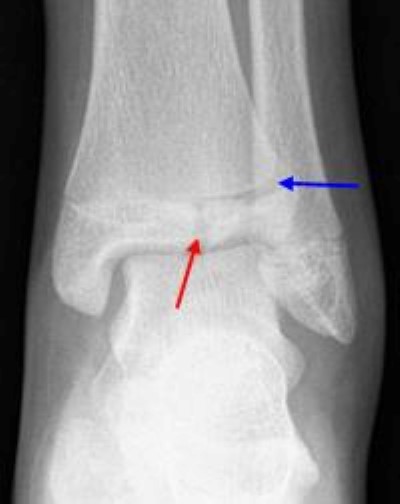

A stress fracture of the ankle also known as a hairline fracture is a small micro fracture of the bone. Ankle fracture causes when you stress an ankle joint beyond the strength of its elements you injure the joint. Stress fractures of the foot and ankle a stress fracture is a small crack in a bone or severe bruising within a bone.

Ankle fractures almost always occur during a traumatic event to the body. If only the ligaments give way and tear you have sprained the ankle. Stress fracture ankle symptoms include pain swelling and immobility.

Hairline fracture ankle healing tips if you want to speed up the process of healing refrain from doing activities. Common signs of an ankle fracture include pain swelling bruising and an inability to bear weight on the broken ankle. Hairline fractures are minute cracks on the bones which can become severe if not treated immediately.

Hairline fracture ankle. Most stress fractures are caused by overuse and repetitive activity and are common in runners and athletes who participate in running sports such as soccer and basketball. Numbness in the affected area. Swelling in the affected area.